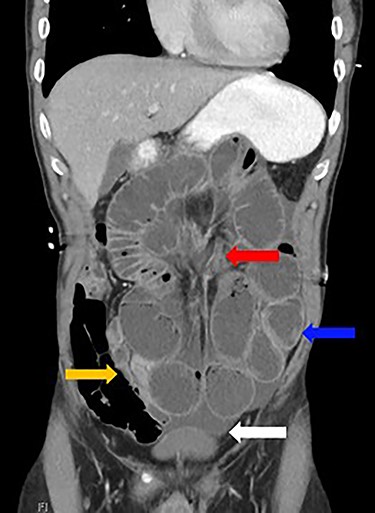

Dilated loops of small bowel (blue arrow), transition point (red arrow), free fluid (evidence of CA; white arrow) and collapsed small bowel (orange arrow).